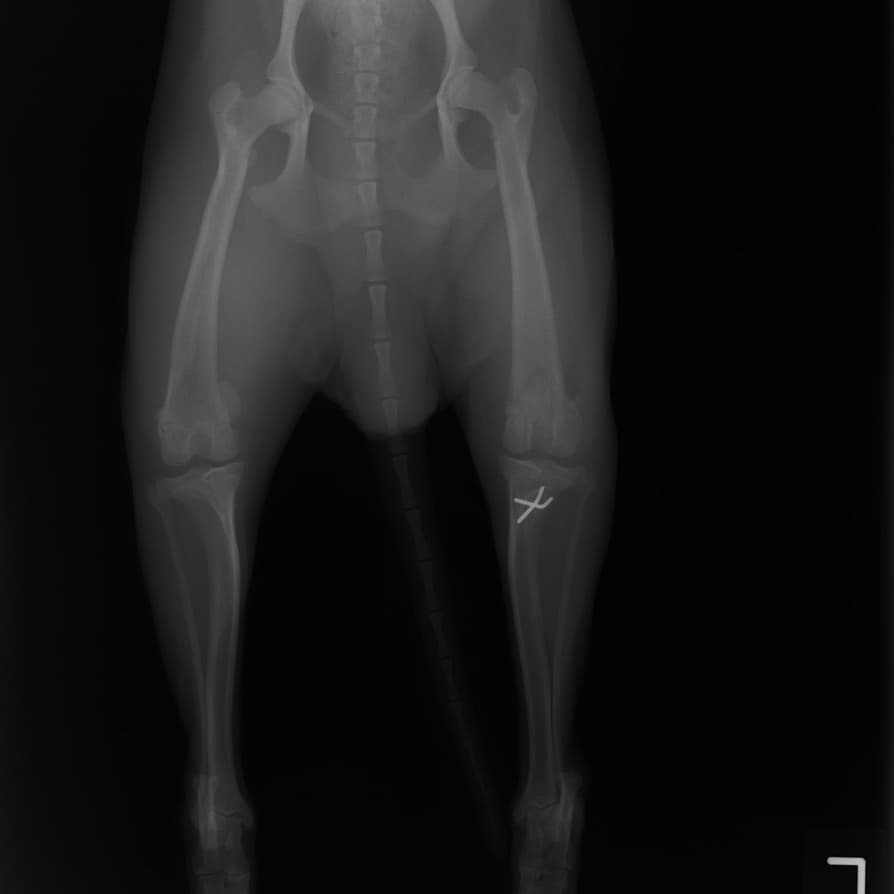

■ 症例20 ポメラニアン 8ヶ月 1.8kg

左右膝蓋骨脱臼 グレードⅢ

2ヶ月前から間欠的跛行が認められ、両膝の膝蓋骨脱臼整復術を行った。

手技は縫工筋及び内側広筋の解放、脛骨粗面の外側転位、滑車ブロック形造溝術、内外側関節包の縫縮を選択し実施した。

右側の膝蓋骨脱臼は上記手技で整復されたものの、左側はそれのみでは膝蓋骨が浮く様子が認められた。その為、PDS縫合糸にて膝蓋靱帯を1糸のみ縫合し、靱帯の縫縮を行った。

膝蓋骨脱臼は膝関節における膝蓋骨の内外側の脱臼と定義されるが、時として単純な内外の脱臼ではなく、膝蓋骨が大きく前方に浮き上がるように脱臼する場合がある。特にトイプードルやポメラニアンといった犬種に多く認められる。

内側脱臼に加えて前方への浮き上がりを矯正する為に、従来より脛骨粗面転移により膝蓋靭帯を外方と下方に引っ張り、固定する方法を選択する。膝蓋骨の前方への浮き上がりが軽度の場合は、従来法ではなく関節包の縫縮で対応していた。しかし、一部の症例で膝蓋骨の動きが悪くなり伸展機構が円滑に機能せずロボット様歩行になるケースがあった。

その為、膝蓋靭帯自体を縫縮する方法を採用した。この方法により、膝関節の伸展機構を妨げず膝蓋骨の軽度の浮きを矯正することが可能となった。

本症例の経過は良好である